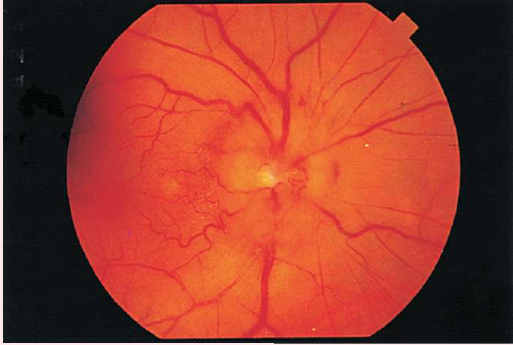

GLAUCOMA

• Enlarged physiologic cup occupying more than half of the disc's diameter

• Pale base of enlarged physiologic cup

• Obscured and/or displaced retina vessels